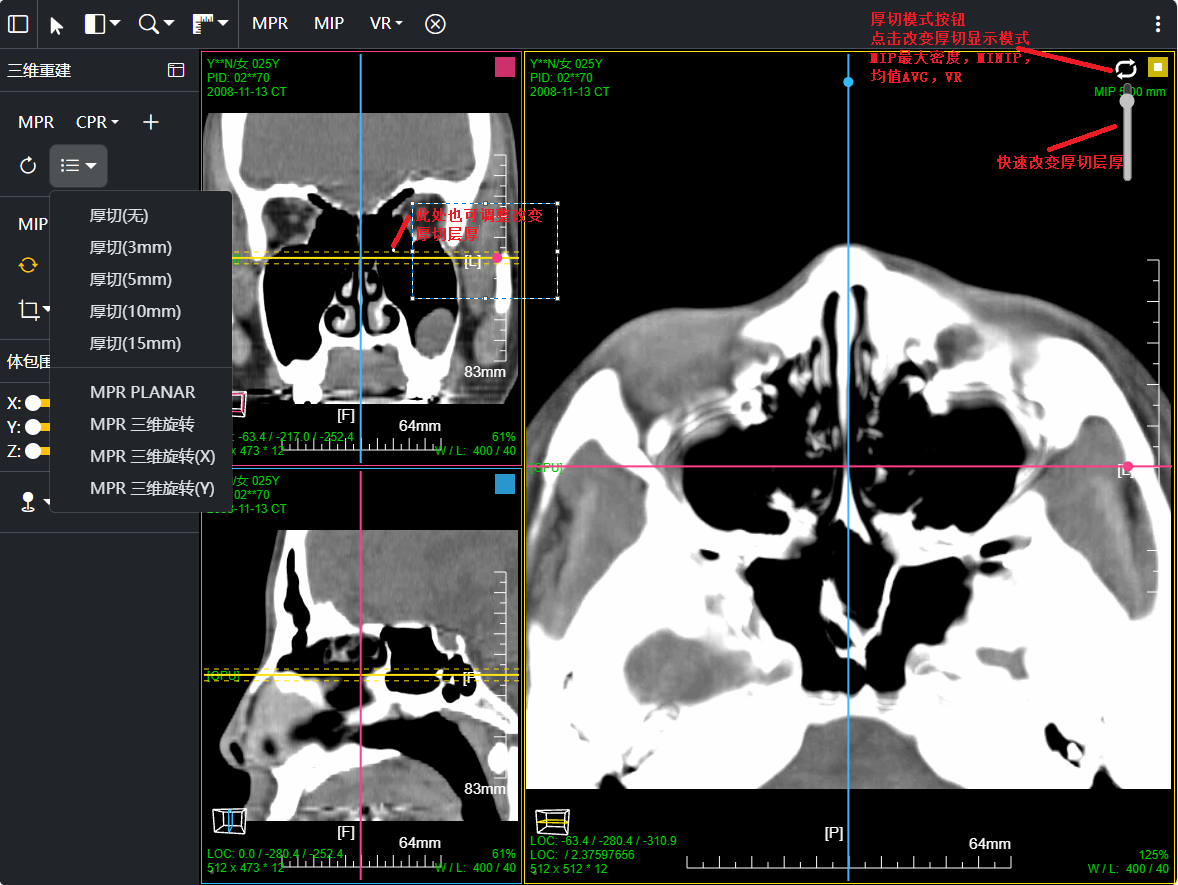

八、三维浏览功能操作和截图

左键双击MPR窗口可在MPR三窗口和1x1窗口间切换;三维渲染窗口左键双击在在1x1视图模式和当前视图模式切换

点击MPR窗口右上角颜色块可AXIS轴位、CORO冠位、SAGI矢位切片切换

鼠标右键点击MPR窗口左下 切片位置指示器 可显隐十字交叉线; 左键点击MPR复位

鼠标左键点击MIP窗口左下 三维旋转状态指示器 可快速旋转到指定面; 右键点击三维旋转复位

厚切支持MIP最大密度 、MINIP最小密度、AVG均值密度、以及VR渲染

改变厚切层厚:1、预设层厚菜单(可配置) 2、拖动滑块快速改变 3、拖动十字交叉线上的层厚虚线

CPR曲面重建 、厚切曲面;